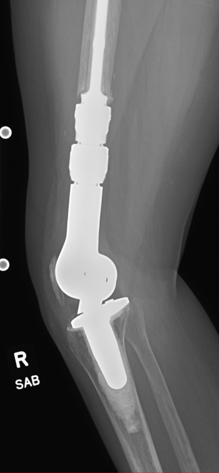

Case: 35 yo F w/ hx of osteosarcoma with painful right DFR. Progressive RLL about femoral stem. Reconstructive options? How to achieve fixation of femoral component?

Right knee passive ROM 0-30. Stiff and painful. Infection has been ruled out.

Reconstructive options include revision DFR, AKA +/- osseointegrated prosthesis, or rotationplasty. After extensive discussion, rotationplasty selected in this case!